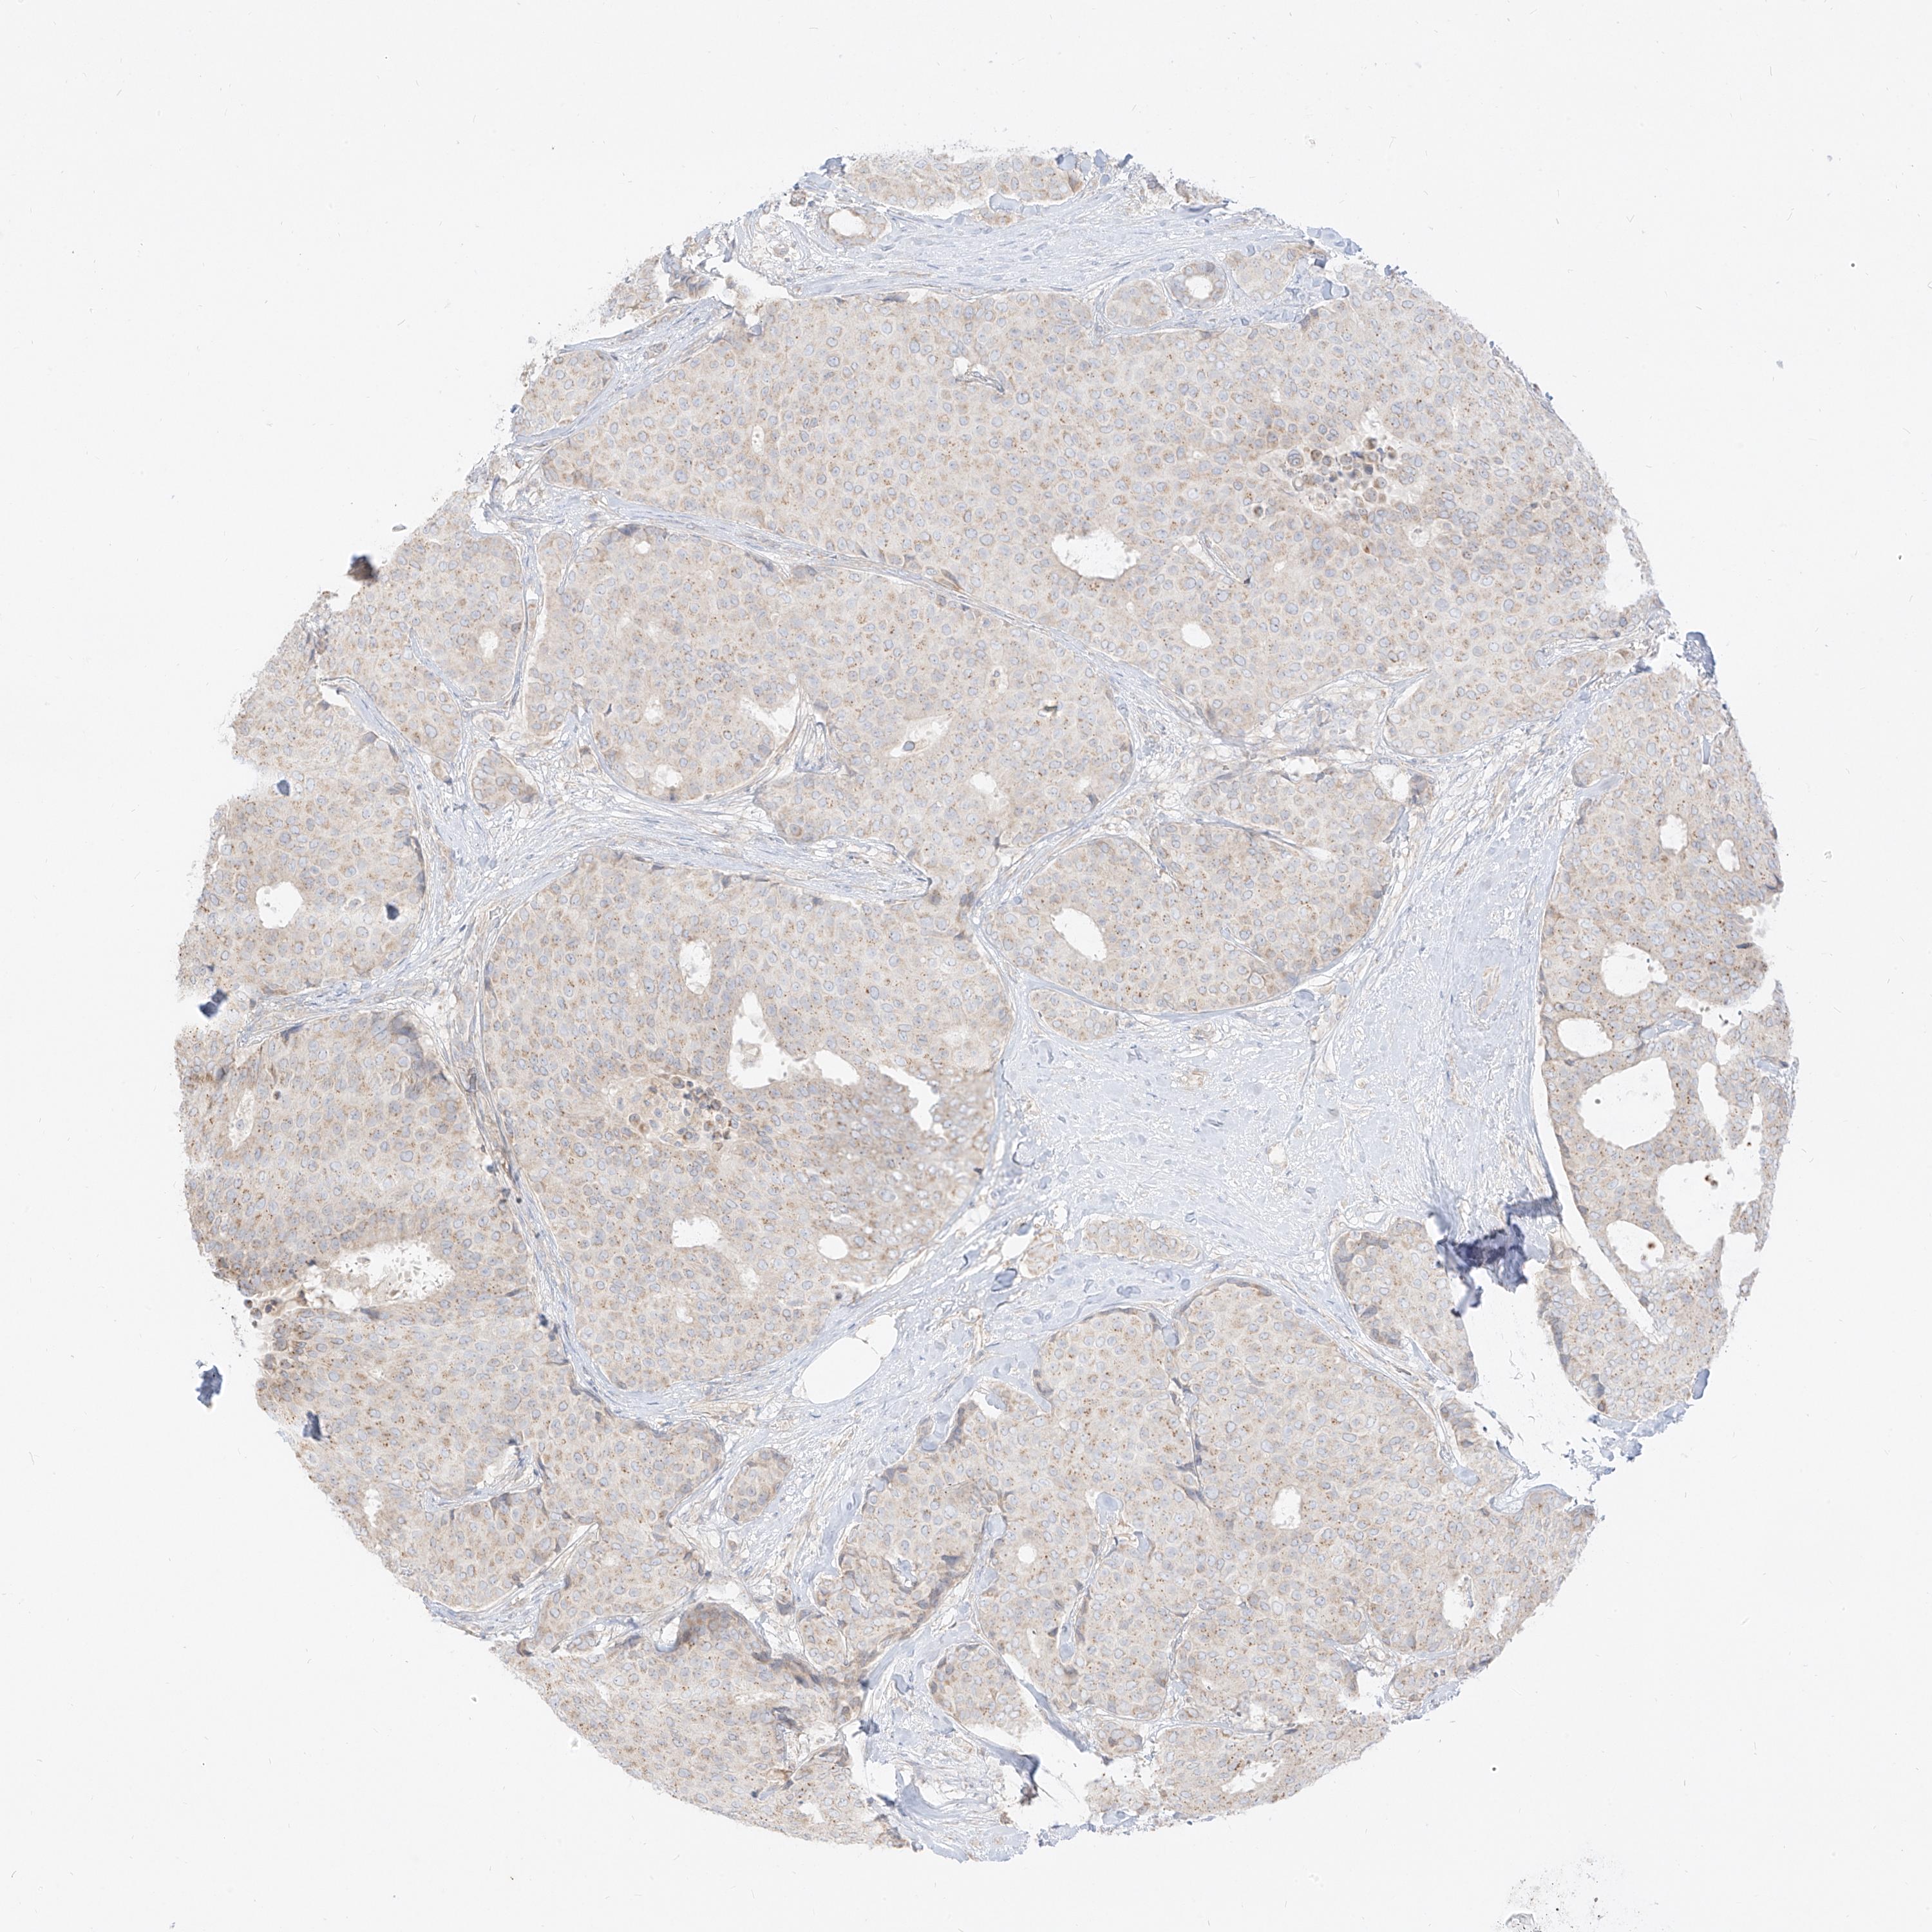

CANCER BREAST CANCER Show tissue menu

BRCA TCGA BRCA VALIDATION PROTEIN EXPRESSION